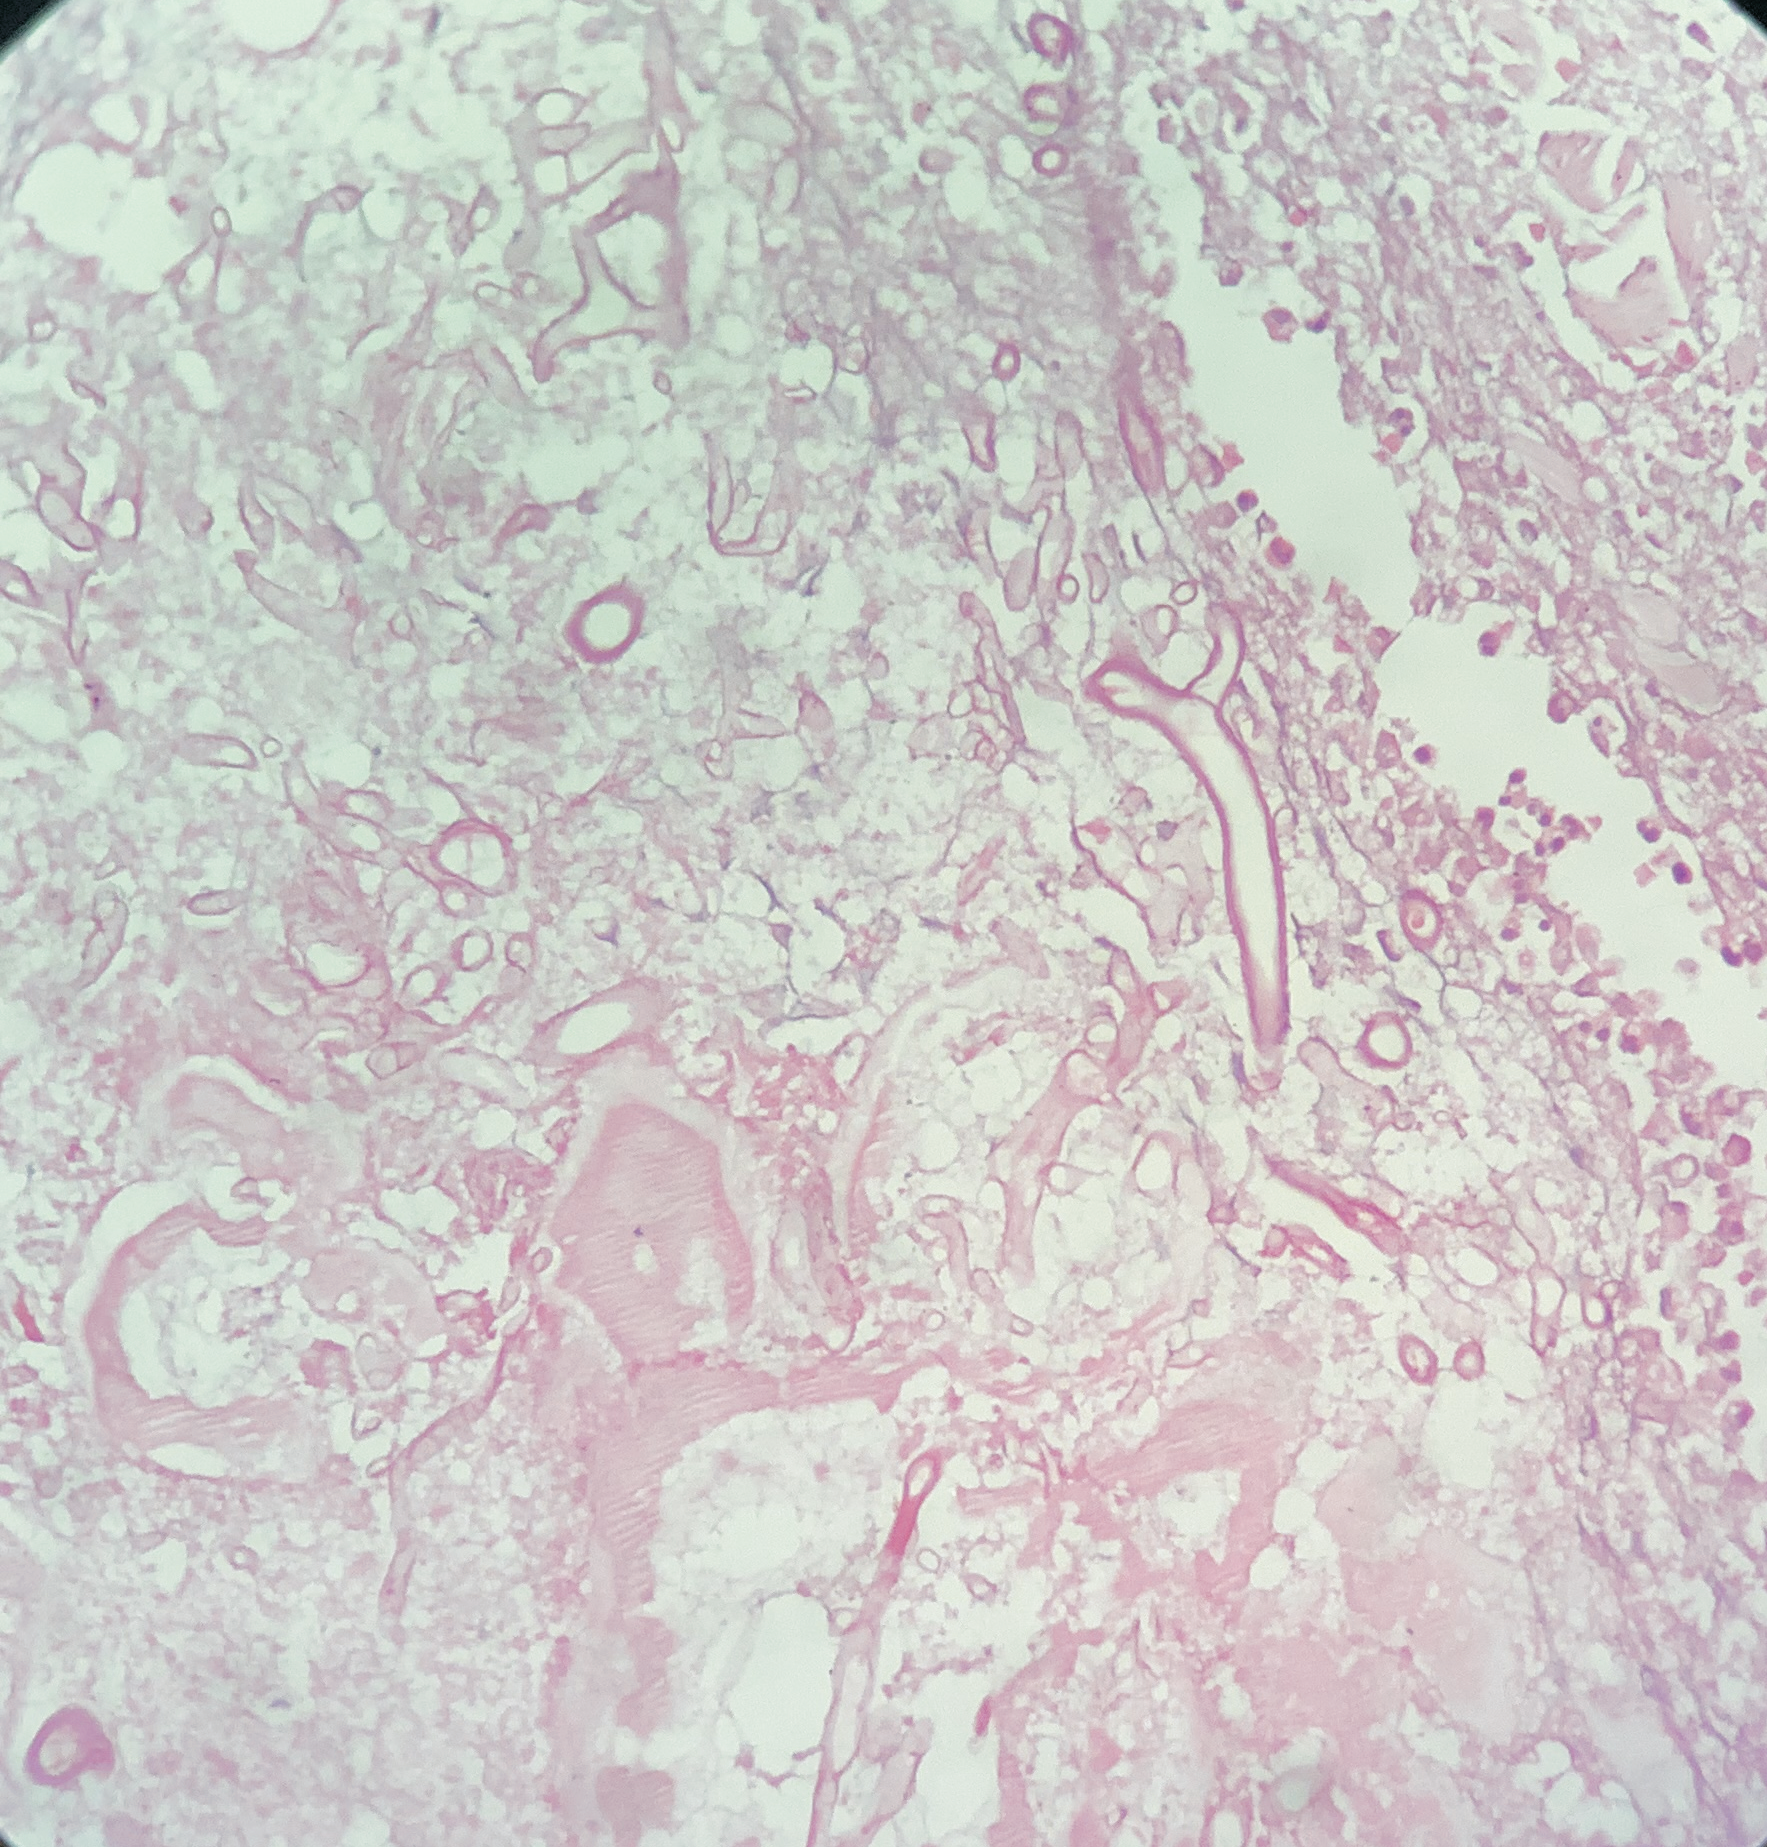

A 76-year-old female presented with multiple fluid-filled painful skin lesions all over the body for the past three months. The patient was normal for three months, later she developed multiple red raised itchy lesions over her hands followed by development on the chest. These lesions progressively increased in number and progressed to the whole body sparing the oral mucosa, genitals, palms, soles and scalp. This fluid-filled lesion did not rapture on pressure and tended to heal. The lesions were associated with pain, acute in onset, penetrating type with a moderate intensity which was relieved on taking medications. No history of pus discharge from these lesions neither there was any history of drug intake. She did not have any history of allergens. She was a known case of Diabetes Mellitus and hypertension. ECG was done which was suggestive of inferior wall ischemic changes for which cardiology reference was done after which 2D ECHO was done which was suggestive of CAD with concentric LVH with normal LVEF(56%) and mild MR. The patient was suggestive for CAG but she refused hence conservative management was done. On Examination Nikolsky's sign was negative while the bullae spread sign could not be elicited. A biopsy of the lesion was done which on histopathology revealed a subepidermal blister with eosinophilic-rich infiltrates in the papillary dermis. She was diagnosed with bullous pemphigoid and was treated with corticosteroids, antibiotics and topical ointments. On Post-treatment head to toe examination, there was a necrotic skin patch of about 4x4 cm over the right scapular region with a line of demarcation, with healthy surrounding skin with no active bleed or pus discharge (Figure 1). Surgery consultation was done and necrotic tissue was excised and sent for histopathological examination. Gross examination showed a fibro-fatty skin-covered tissue piece measuring 8.5 x 4.5 x 2.0 cm. The skin surface was necrosed. The cut surface was grey-brown to grey-yellow. When the microscopic examination was done sections showed ulcerated skin surface with necroinflammatory exudates viable epidermal lining or skin adnexa noted. Underneath the ulcerated surface, there was predominantly necrotic tissue, dense fibrin-inflammatory exudates, foci of fat necrosis, hhemorrhage, and congested to thrombosed blood vessels. Also noted are many scattered broad non-branched aseptate fungal hyphae infiltrating into fibro-fatty tissue collagenous septae and occasional vessels as well (Figure 2). PAS and GMS stain highlighted aseptate broad fungal hyphae confirming mucormycosis (Figure 3,4). Thus a final diagnosis of Invasive Mucormycosis with extensive necrosis was made. The patient was treated with anti-fungal drugs (Amphotericin B) and was kept on follow-up. After one month she succumbed to death due to coronary heart disease leading to heart failure.

![Periodicacid schiff stain highlighting aseptate broad fungal hyphae [400X]](https://s3-us-west-2.amazonaws.com/typeset-prod-media-server/c5743307-b164-4e88-a493-3f03bf7131d0image3.png)